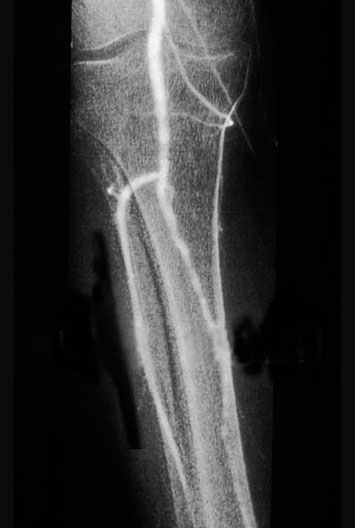

Popliteal Artery Arteriogram

1. Femur

2. Anterior tibial artery

3. Fibula

4. Popliteal artery

5. Tibia

6. Posterior tibial artery